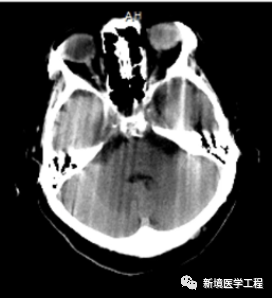

各种成像模式的原理和伪像发生的机制

伪像常见的表现机制;